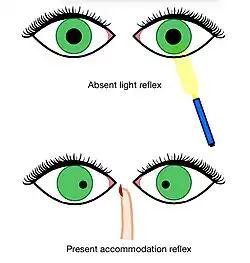

Parenchymal syphilis occurs in the late stage of neurosyphilis, with average presentation occurring 15 to 25 years after initial infection.[3] This stage of the disease is generally in the form of tabes dorsalis or general paresis. Tabes dorsalis, also called locomotor ataxia, describes a constellation of symptoms resulting from a degenerative process of the posterior columns of the spinal cord. Symptoms include pain, ataxic wide-based gait, paresthesias, bowel or bladder incontinence, loss of position and vibratory sense, acute episodic gastrointestinal pain, Charcot joints, and reduced reflexes.[6] The Argyll Robertson pupil, which is a condition where the pupils do not constrict to bright light but constrict when focusing on a near object (accommodation reflex), is another feature that may be present.[10]